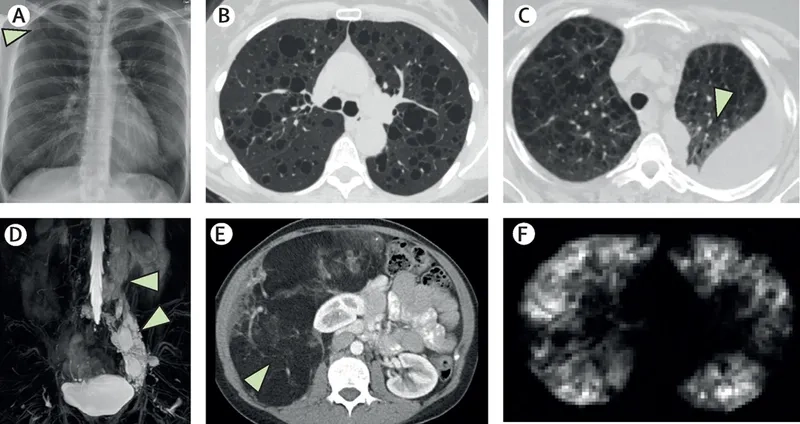

Image of the disease Lymphangioleiomyomatosis